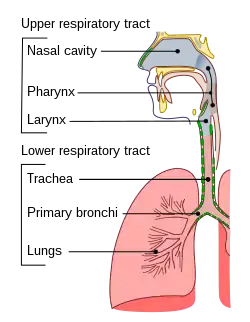

The trachea (pl.: tracheae or tracheas), also known as the windpipe, is a cartilaginous tube that connects the larynx to the bronchi of the lungs, allowing the passage of air, and so is present in almost all animals with lungs. The trachea extends from the larynx and branches into the two primary bronchi. At the top of the trachea the cricoid cartilage attaches it to the larynx. The trachea is formed by a number of horseshoe-shaped rings, joined together vertically by overlying ligaments, and by the trachealis muscle at their ends. The epiglottis closes the opening to the larynx during swallowing.

An adult's trachea has an inner diameter of about 1.5 to 2 centimetres (1⁄2 to 3⁄4 in) and a length of about 10 to 11 cm (4 to 4+1⁄4 in), wider in males than females.[2] The trachea begins at the lower edge of the cricoid cartilage of the larynx[3] at the level of sixth cervical vertebra (C6)[2] and ends at the carina, the point where the trachea branches into left and right main bronchi.[2], at the level of the fourth thoracic vertebra (T4),[2] although its position may change with breathing.[3] The trachea is surrounded by 16–20 rings of hyaline cartilage; these 'rings' are 4 millimetres high in the adult, incomplete and C-shaped.[2] Ligaments connect the rings.[3] The trachealis muscle connects the ends of the incomplete rings and runs along the back wall of the trachea.[3] Also adventitia, which is the outermost layer of connective tissue that surrounds the hyaline cartilage, contributes to the trachea's ability to bend and stretch with movement.[4]